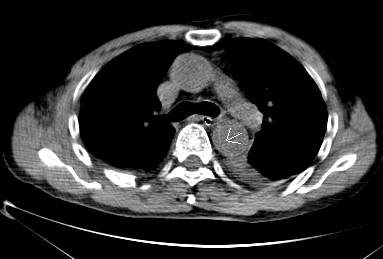

平扫CT提示主动脉弓层面及右肺动脉层面均可见主动脉血管腔内的内膜片影(红色箭头所示),CTA显示为A型主动脉夹层。